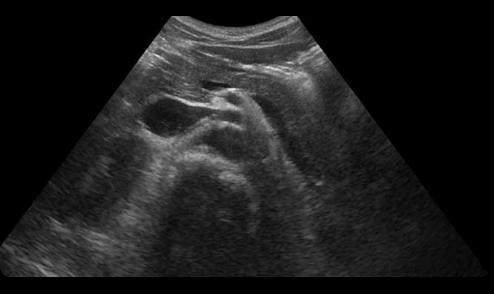

超音波検査装置については大学病院級のものを導入し、女性のベテラン超音波専門技師による腹部エコー、頚動脈エコー、甲状腺エコー、心エコー、乳腺エコーを提供しております。

超音波検査

当院での超音波検査には、『ALOKA ARIETTA S70』(日立アロカメディカル社)を使用しております。